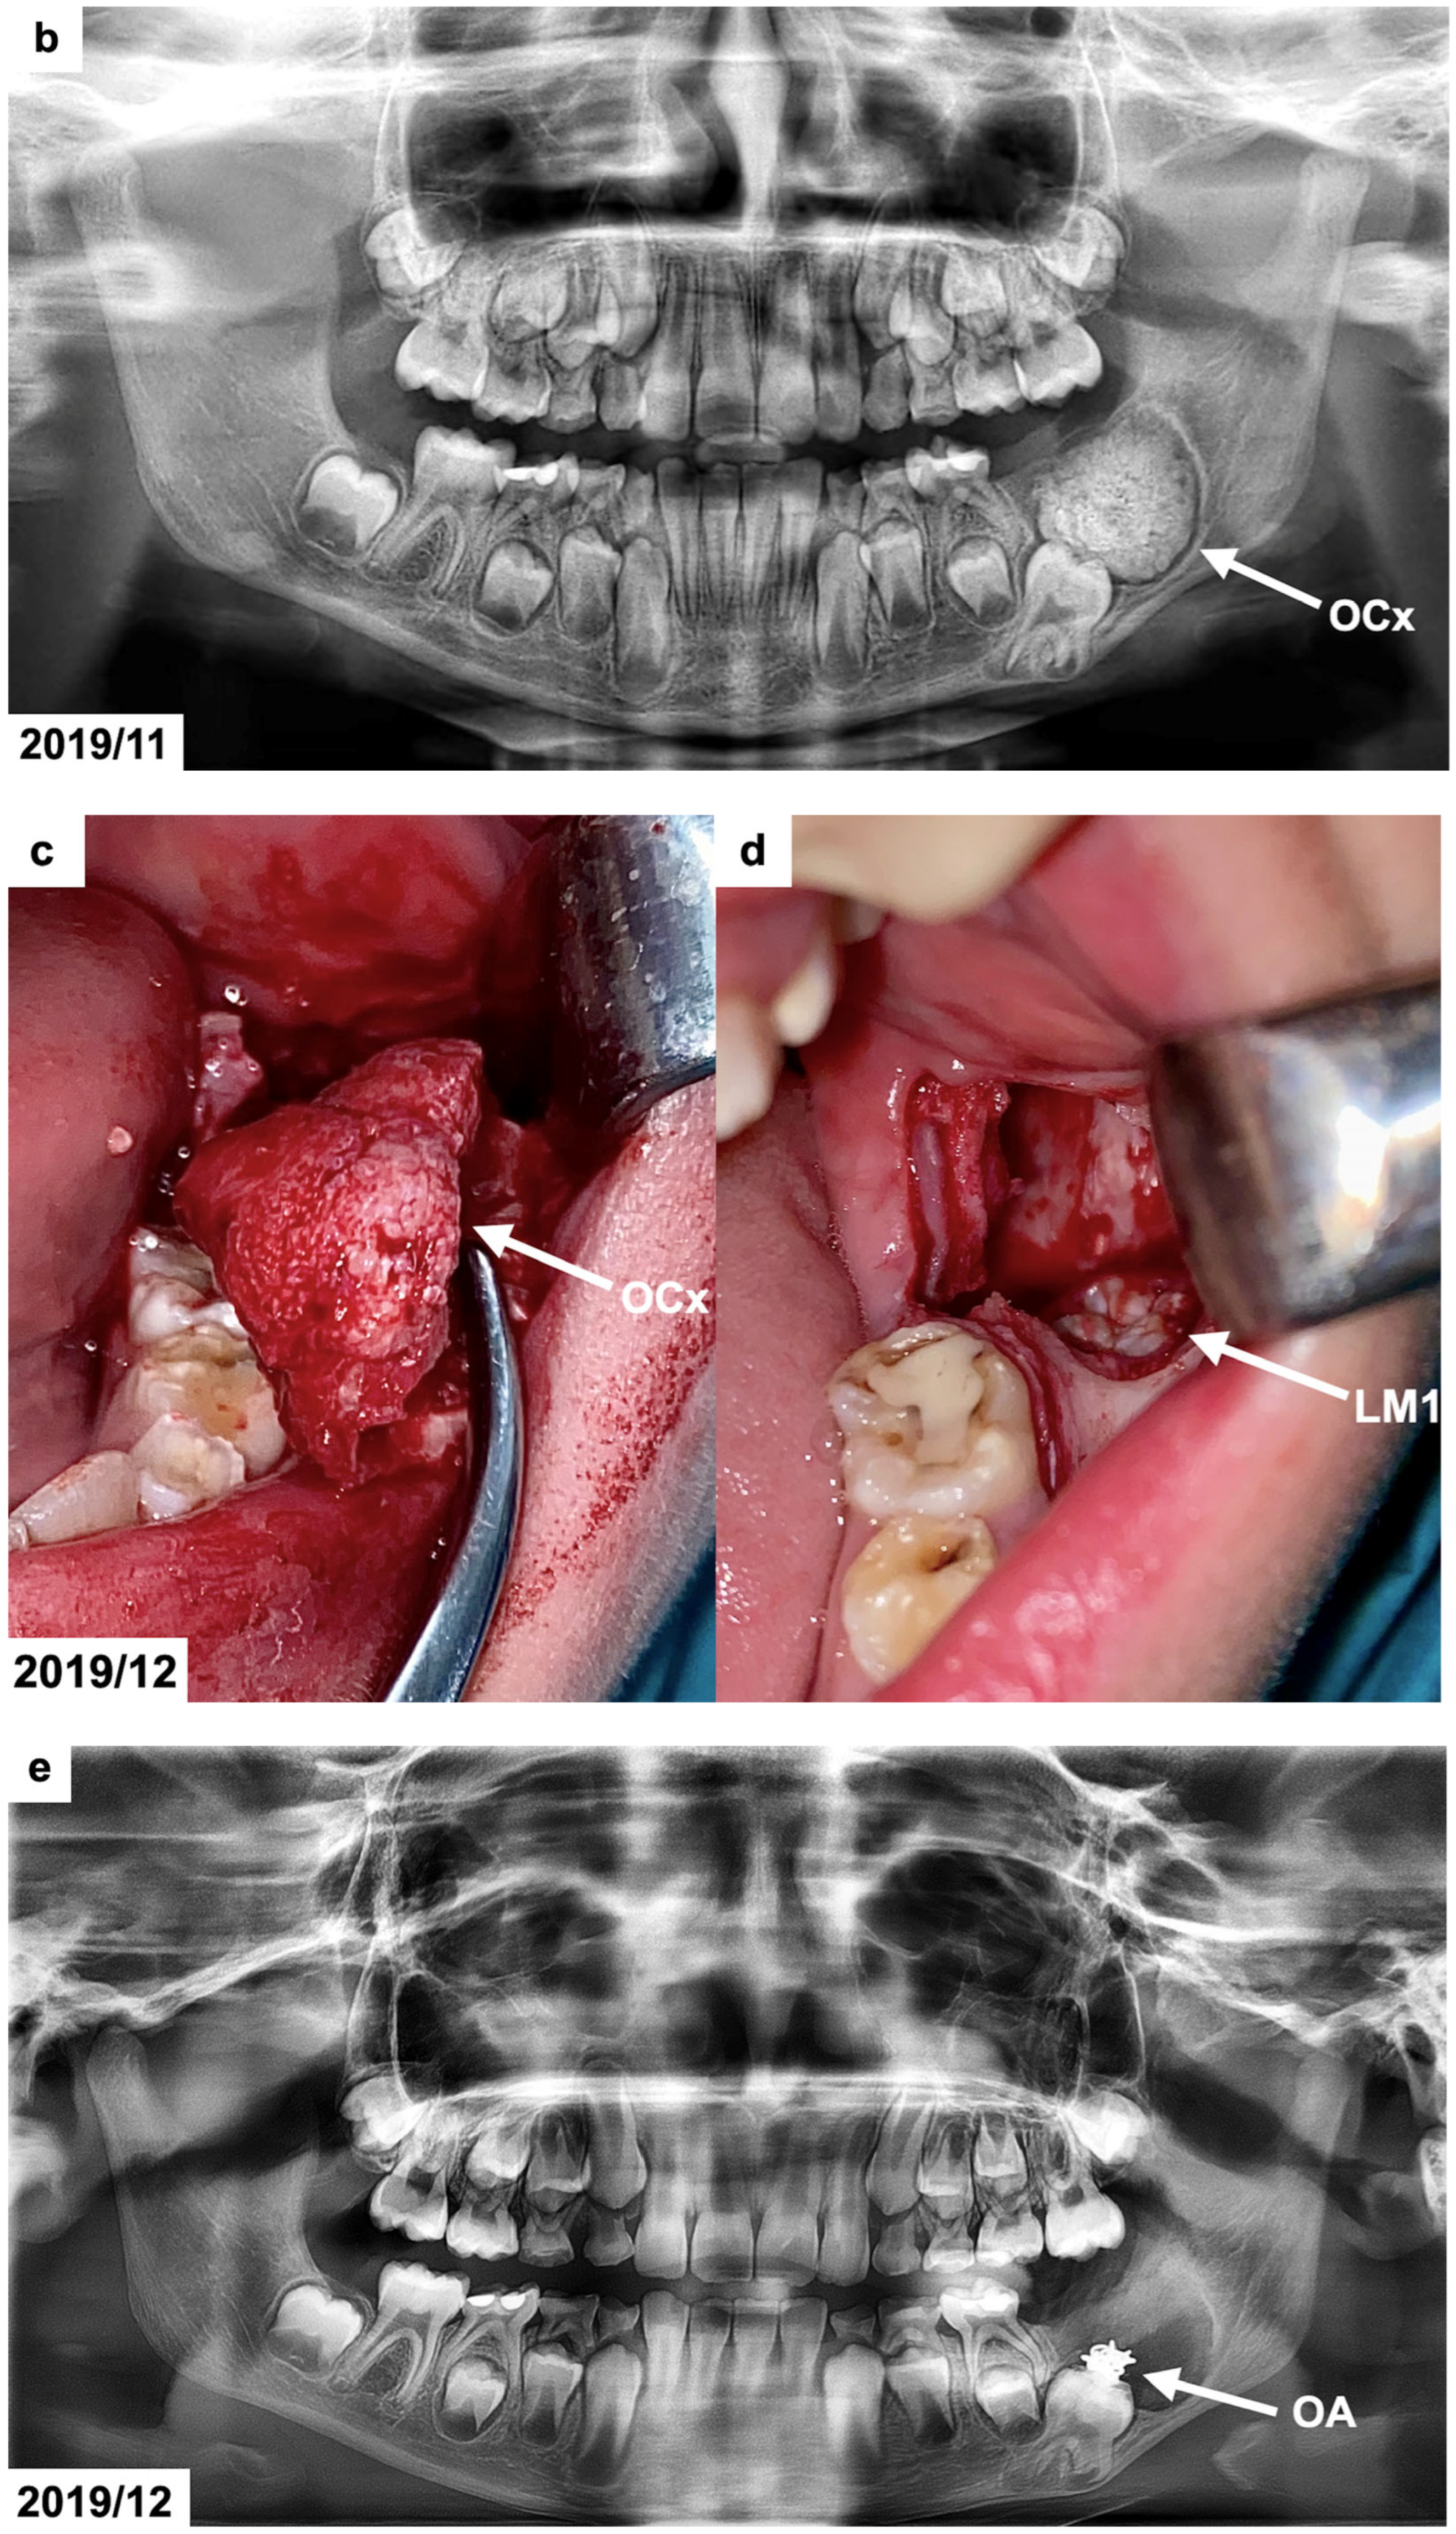

Figure 1.

(a) Intraoral photographs before surgical and orthodontic treatment. The patient was 8 years and 10 months old. (b) Panoramic radiograph before the treatment, presenting the odontogenic tumor in the left mandible molar region (OCx = complex odontoma). The patient was 8 years and 10 months old. (c,d) Intraoral photographs taken during the surgical removal of the tumor exposing the occlusal surface of the permanent lower left first molar (OCx = complex odontoma, LM1 = lower left first permanent molar). The patient was 8 years and 11 months old. (e) Panoramic radiograph after the surgical treatment and bonding of the orthodontic attachment (OA = orthodontic attachment). The patient was 8 years and 11 months old. (f) Panoramic radiograph 1 year after the removal of the tumor showing the orthodontic attachment bonded to the occlusal surface of the permanent lower left first molar (OA = orthodontic attachment). The patient was 10 years and 1 month old. (g) Intraoral photographs of spontaneously erupted permanent lower left first molar after removal of the orthodontic attachment. The patient was 10 years and 11 months old. (h) Panoramic radiograph 4 years after the surgical and orthodontic treatment (LM1 = lower left first permanent molar). The patient was 12 years and 7 months old. (i) Intraoral photographs 4 years after the surgical and orthodontic treatment showing the erupted permanent lower left first molar and its position in the dental arch. The patient was 12 years and 7 months old.

The panoramic radiograph (Figure 1b), which was provided by the patient, indicated the presence of a calcified lesion with a radiolucent rim and an adjacent cortical bone layer with a diameter of approx. 3 cm at the distal area of the mandibular first permanent molar. To precisely define the size and position of the tumor, the patient was referred for cone-beam computed tomography (CBCT). The CBCT examination showed a focal area with a calcified mass with the radiodensity of hard dental tissues surrounded by a narrow radiolucent zone on the left side in the molar region of the mandible. The dimensions of the lesion were 25 × 20 × 17 mm. The radiological picture indicated the presence of a complex odontoma. This lesion extended to the lower border of the mandible. The position of the neighboring first permanent molar was altered by the tumor as the tooth was moved downward and mesially. The roots of the affected molar were still developing (app. 2/3 of the final root length). The upper part of the tumor was not covered by the alveolar bone by 20 × 6 mm.

The surgery was performed under local anesthesia using lignocaine 2% with noradrenaline. In the retromolar area of the mandible, a triangular incision and a mucoperiosteal flap retraction were performed, exposing the rough surface of the tumor and the adjacent bone. A bony layer covering the lesion topically and buccally was removed using a round surgical bur with constant saline solution irrigation. After the tumor exposure, it was separated and removed entirely without damaging the unerupted first permanent molar (Figure 1c,d). The cavity was rinsed with a Metronidazole solution. The orthodontic attachment was bonded to the occlusal surface of the exposed tooth (Figure 1e). The flap was repositioned, and sutures were placed. The removed tumor was submitted for histopathological examination. Post-operatively, the patient was given an antibiotic (amoxicillin 500 mg/clavulanic acid 125 mg) every 12 h for 7 days. A follow-up visit was scheduled after 7 days of uneventful healing, and the sutures were removed. No post-operative complications were noted.

The lower removable plate with an extension to attach the elastic from the button bonded on the exposed impacted molar was prepared in March 2020. However, due to the eruption of the COVID-19 pandemic, it was not delivered to the patient after surgery. The university clinic was only treating emergencies for the next few months, and the patient came back after 1 year, in February 2021. The patient reported a spontaneous eruption of the impacted maxillary. The occlusal surface of the lower left first permanent molar with a bonded button was visible during the clinical examination. The panoramic radiograph (Figure 1f) revealed a distinct occlusal movement of the impacted tooth and normal healing after the removal of the tumor. In December 2021, the mandibular left first permanent molar erupted in the oral cavity (Figure 1g). No pathologies were present on the panoramic radiograph except for the bending of the distal root of the affected molar. The patient has received an activator with an expansion screw to correct his Class II relations and maxillary crowding. In August 2023, the impacted molar tooth erupted into occlusion, and the root development was finished (Figure 1h,i). A marked dilaceration of its distal root could be noticed, which was caused by the presence of a tumor in proximity to the developing, neighboring first molar. The prognosis of the affected molar was estimated as favorable in the long term if good oral hygiene is maintained. A complete regeneration of the alveolar bone defect was also seen. No other permanent molars on the side of the tumor were present on the radiograph. Orthodontic treatment with a removable appliance is continued.